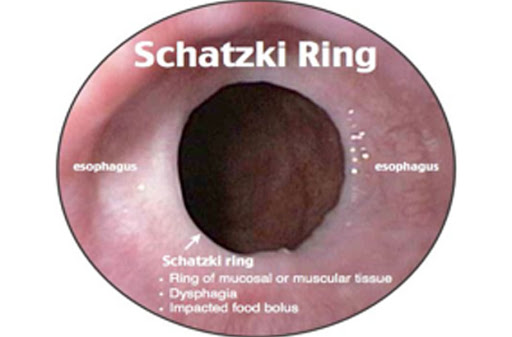

Ringe & Webs

- Dünne Schleimhaut Membranen im Ösophagus → mechanische Engstellen.

- Schatzki-Ring (distal, meist mit Hiatushernie) → Dysphagie für feste Speisen.

- Diagnostik: Breischluck oder Endoskopie.

- Therapie: Endoskopische Dilatation, Eisen-Substitution (bei PVS).

- Schatzki-Ring = Dysphagie bei fester Nahrung.